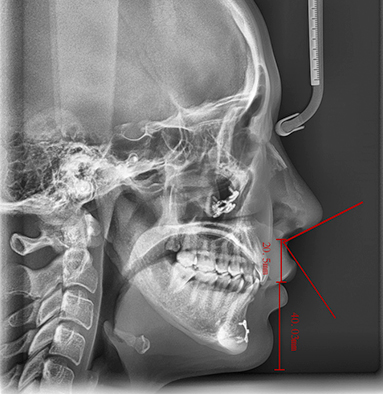

단순히 코끝만 높인다고 해서 돌출입이 개선되거나 세련된 옆모습이 완성되지는 않습니다.

리트머스성형외과의 비순각 교정술은 코끝과 인중의 비율을 함께 고려하여,

좁아진 비순각의 이상적인 각도와 인중 길이를 정밀하게 교정하는 방식으로 진행됩니다.

이를 통해 단순히 코 모양만 바뀌는 것이 아니라,

얼굴 전반의 균형이 잡히고, 돌출입이 자연스럽게 개선되며, 옆모습이 입체적이고 세련되게 변화합니다.

특히 정승일 대표원장의 노하우가 담긴 리트머스의 맞춤 디자인은,

개개인의 얼굴 골격과 조화를 고려한 정밀한 교정으로 가장 이상적인 비순각과 옆라인을 찾아드립니다.